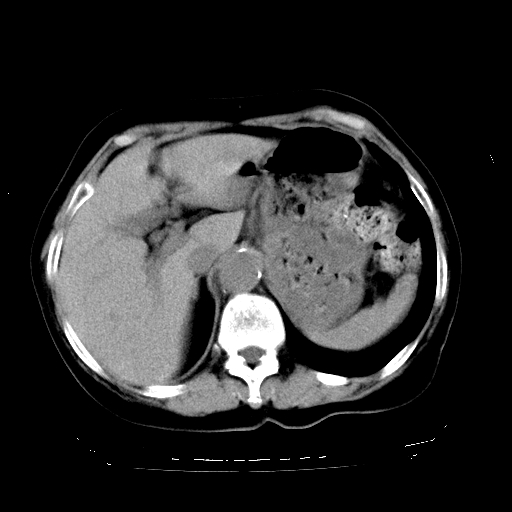

标题: CT23991:女,72岁,咳嗽、憋气一周。 [打印本页]

女,72岁,咳嗽、憋气一周,十年前曾患肺结核及胸膜结核。

1.右侧损毁肺伴胸膜钙化,2.左肺小结节灶,良性可能大,注意复查。3.肝脏左叶囊肿。4.先天性一侧肺不发育待出外(右侧胸廓无明显塌陷)。对比原片应该非常有帮助。

肝脏转移

支持楼上,肝脏多发囊肿